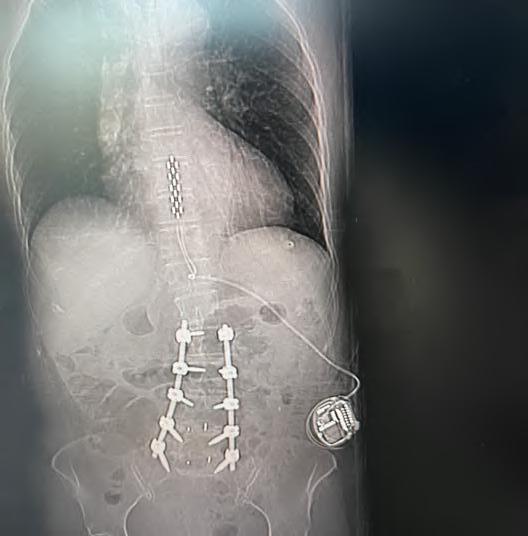

En enero de 2025, el equipo de columna de Clínica Bupa Santiago realizó una cirugía para el tratamiento de dolor crónico intratable, mediante la implantación de un estimulador medular de última generación. El procedimiento fue liderado por el Dr. Miguel Naranjo, traumatólogo especialista en columna, y marca un hito en el abordaje del dolor lumbar persistente, especialmente en pacientes que han agotado otras alternativas terapéuticas.

La paciente, con antecedentes de dolor lumbar crónico, había sido intervenida hace nueve años con una fijación y artrodesis de columna, sin lograr una resolución completa del dolor pese a múltiples tratamientos. Frente a este escenario, y tras una cuidadosa evaluación, se optó por implantar un estimulador medular como última alternativa terapéutica.

Tecnología avanzada al servicio de la calidad de vida

La cirugía consistió en la instalación de una placa de electrodos sobre la médula espinal, conectada a un generador que se ubicó en la zona abdominal. Este dispositivo emite impulsos eléctricos que bloquean la sensación de dolor antes de que llegue al cerebro, permitiendo una mejora significativa en la calidad de vida del paciente.

«El uso de esta tecnología ha demostrado una tasa de éxito cercana al 95%, siempre que exista una correcta selección de candidatos», explicó el Dr. Naranjo. «Hoy, gracias al trabajo de un equipo multidisciplinario y a los avances en diagnóstico, podemos ofrecer esta opción a pacientes que antes simplemente no tenían solución».